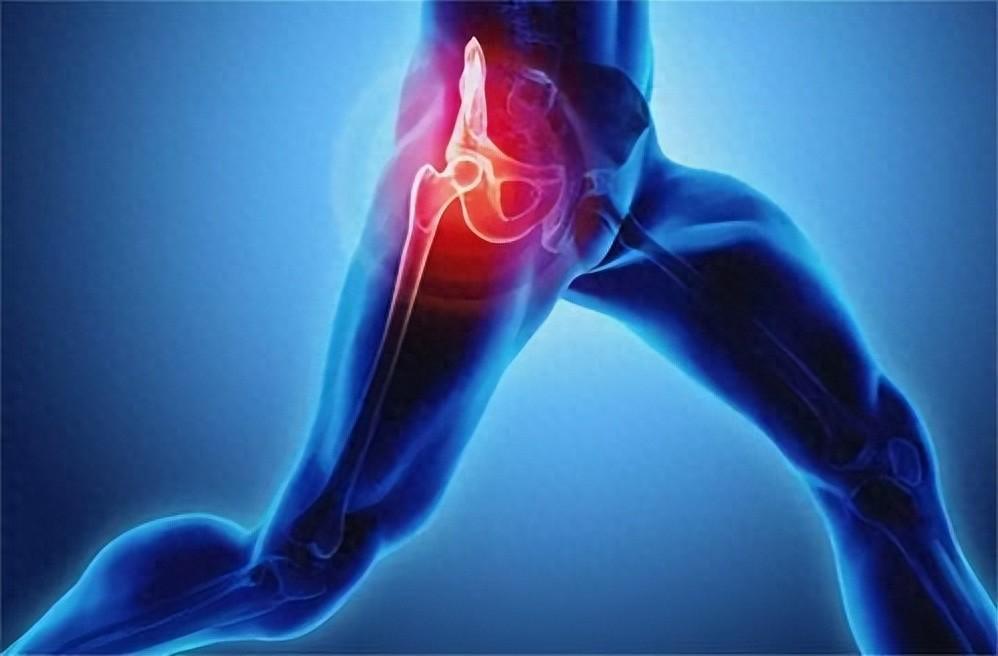

1、腐腥臭是肺癌

當患上肺部疾病時比如肺部感染肺炎、氣管炎、肺癌都會引起口臭,主要是因為患者的肺部積攢了大量粘液所引起的口臭。肺膿腫的患者一般會伴隨腐酸性口臭味,同時也會伴有膿性痰以及發燒,只有去醫院做胸片檢查才能夠確診。支氣管擴張以及肺結核患者會出現血腥味的口臭,晚期肺癌患者會有腐腥口臭味。